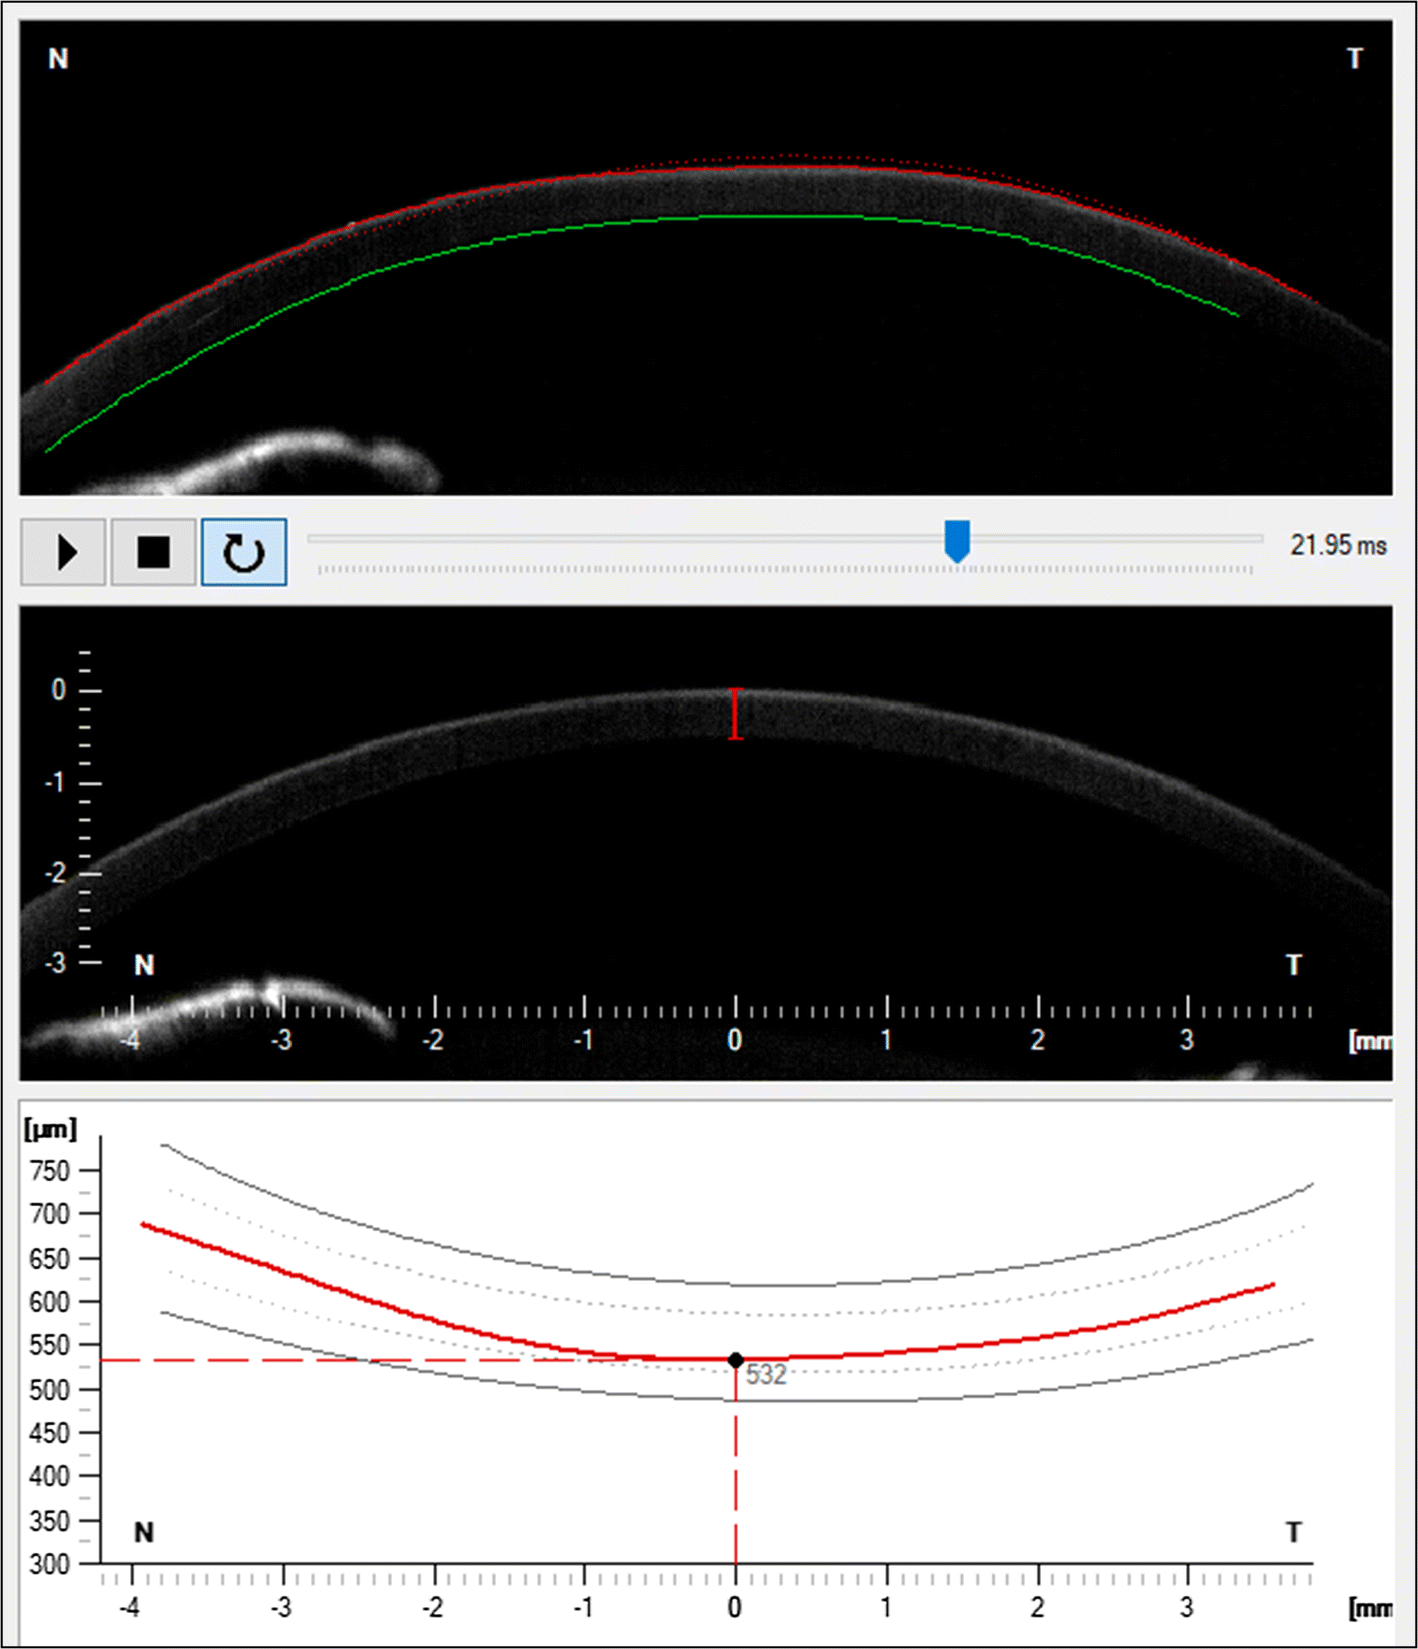

Part of the IOP/Pachy display presenting the possibility of corneal thickness measurement